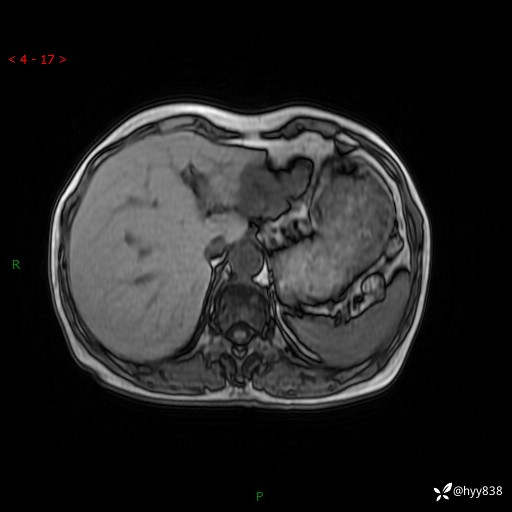

肝脏MRI平扫(同反相位)

增强(动脉期+静脉期+延迟期)